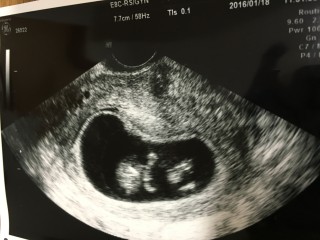

赤ちゃんらしいポーズをしてました。4センチにまで成長しました。心音も聞かせてもらえて泣きそうになりました。

8週目に出血をして切迫流産になり、安静後初めての内診。 内診中に足を伸したり、手を伸す姿が見えて感動しました。